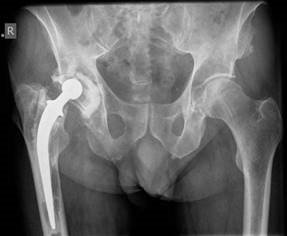

Hip structured oral questions Structured Hip oral examination question 1 EXAMINER : This is a radiograph of a…